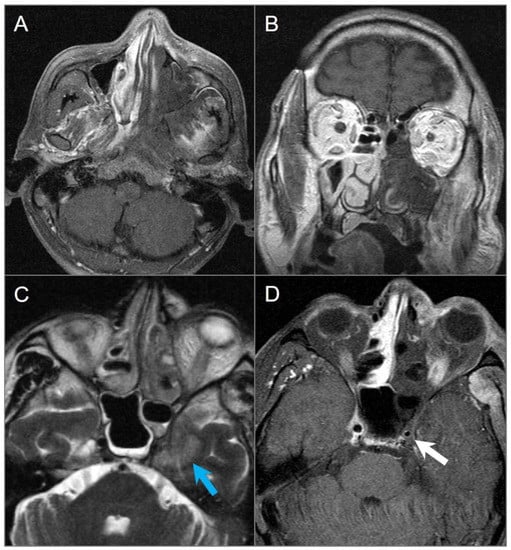

4.1.5. Extension of Head and Neck Malignancy